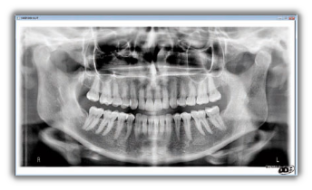

Gendex Orthoralix 8500 DDE vanta un design moderno che combina un’estrema funzionalità e semplicità d’uso con una gradevole estetica high-tech veramente accattivante, che non mancherà di valorizzare il vostro studio. Le immagini sono acquisite in modalità digitale mediante sensore CCD che la più recente ed avanzata tecnologia mette a disposizione. Il sistema dispone di quattro proiezioni: panoramica adulto, panoramica bambino, ATM frontale e ATM laterale.

Posizionato correttamente il paziente, Orthoralix 8500 DDE per mezzo della movimentazione multi-motorizzata dell’assieme monoblocco/sensore è in grado di generare sofisticate proiezioni specifiche per l’obiettivo diagnostico, producendo così immagini fedeli e nitide dell’intera regione dento-maxillo-facciale. L’ingrandimento si mantiene costante durante tutta l’esposizione garantendo immagini panoramiche caratterizzate da una minima distorsione radiografica.

Le immagini del nuovo Orthoralix 8500 DDE sono nitide e definite anche grazie alla piccola macchia focale del tubo radiogeno (solo 0,4 mm la più piccola nel settore). Utilizzando i più recenti algoritmi di elaborazione delle immagini digitali applicati ai dati che compongono la panoramica di questo sistema di nuova generazione, si ottengono radiografie che riproducono con precisione aree anatomiche critiche dei pazienti.